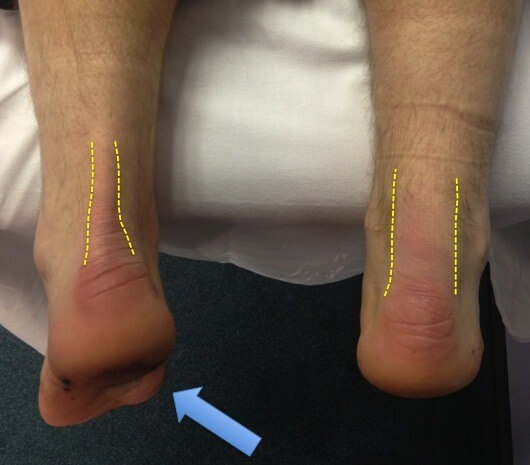

💥𝐀𝐜𝐡𝐢𝐥𝐥𝐞𝐬 𝐓𝐞𝐧𝐝𝐢𝐧𝐨𝐩𝐚𝐭𝐡𝐲💥 ——— 👣Achilles tendinopathy describes a …